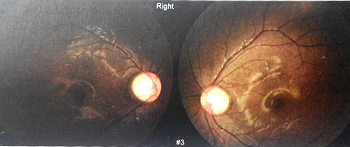

图为在华西医院检查时当时的配镜处方

配镜三个月后,洪洪告诉我,他坐在第一排都看不见黑板上的字。这时老师也打电话来说,我家小孩上课总是开小差。我一听心想:看不见黑板肯定上课要分心。于是二零一二年五月,我们再次来到华西医院進行检查,一检查吓一跳,医生告诉我:“你家小孩的眼睛验光,三百度也只能看到零点八,二百度也是零点八,度数上不去。你带他做一个全面的检查。”于是我们让医生做了全面的检查,下面这些就是当时做眼部OCT时照出来的图片:

OD OCT图

视盘图

最后经过医院医生的确诊,得出的结论是双眼发育性青光眼。原来,洪洪歪着脑袋斜着看是因为眼底正前方可能被强光灼伤(见黄斑区),所以只能歪着脑袋才能正确聚焦。

图为医生当时的检测报告。